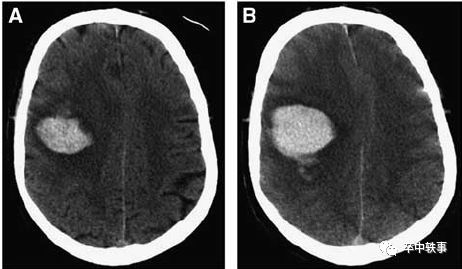

这项研究发现用硅胶软管在急性,亚急性和慢性脑血肿病人抽吸出的陈旧血液量为35.7%,43.3%和50.8%,以慢性血肿效果为好。灌入尿激酶后再抽吸,基本上可以完全清除 CT 影像上的血肿。

与94例开颅清除血肿手术病人相比,Matsumoto 和 Hondo 微创清除血肿手术似乎有减少死亡率和致残率的趋势(样本量太小,上图)。

有人报道在脑出血40-60天后再清除血肿没有导致明显的临床改善,因此,Matsumoto 和 Hondo 提议在脑出血28天后应该 “早点” 清除血肿。

神经功能检查发现在28天内清除血肿对大鼠几乎无帮助,只是在第1-2和第28天时比不清除血肿组有轻微改善(上图)。

组织学检查发现抽吸血肿组脑室扩大和脑萎缩显著减少,但是对脑水肿无益。

作者认为脑出血的原发脑损伤是无法挽救的。脑血肿占位性影响可能减少血肿周围的脑血流,出现类似脑缺血时的半暗带,所以抽出血肿减压,保护了血肿周围的脑细胞。